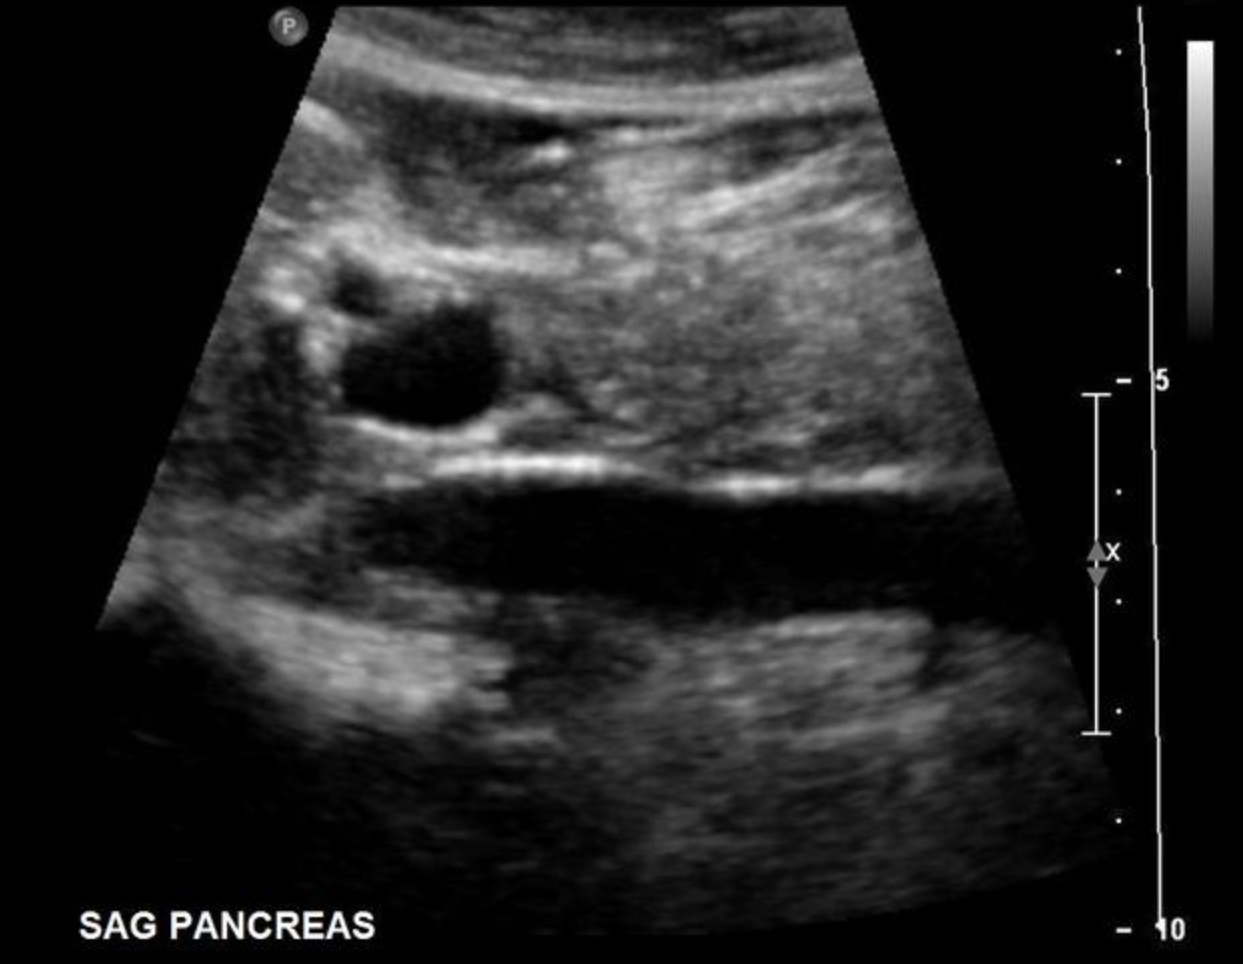

What structure is marked with the X on the image?

Main pancreatic duct